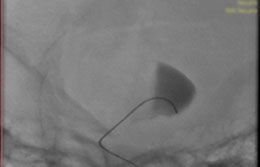

La paciente ingreso al Servicio de Hemodinamia el día martes 11 de febrero con un aneurisma cerebral gigante en la carótida izquierda y se le practicó una embolización; es decir una oclusión por dentro del mismo, donde se colocó un dispositivo denominado coils más un stent diversor de flujo. El procedimiento fue exitoso y contó con la colaboración de médicos neurointervencionistas del Instituto Oulton de la Ciudad de Córdoba.